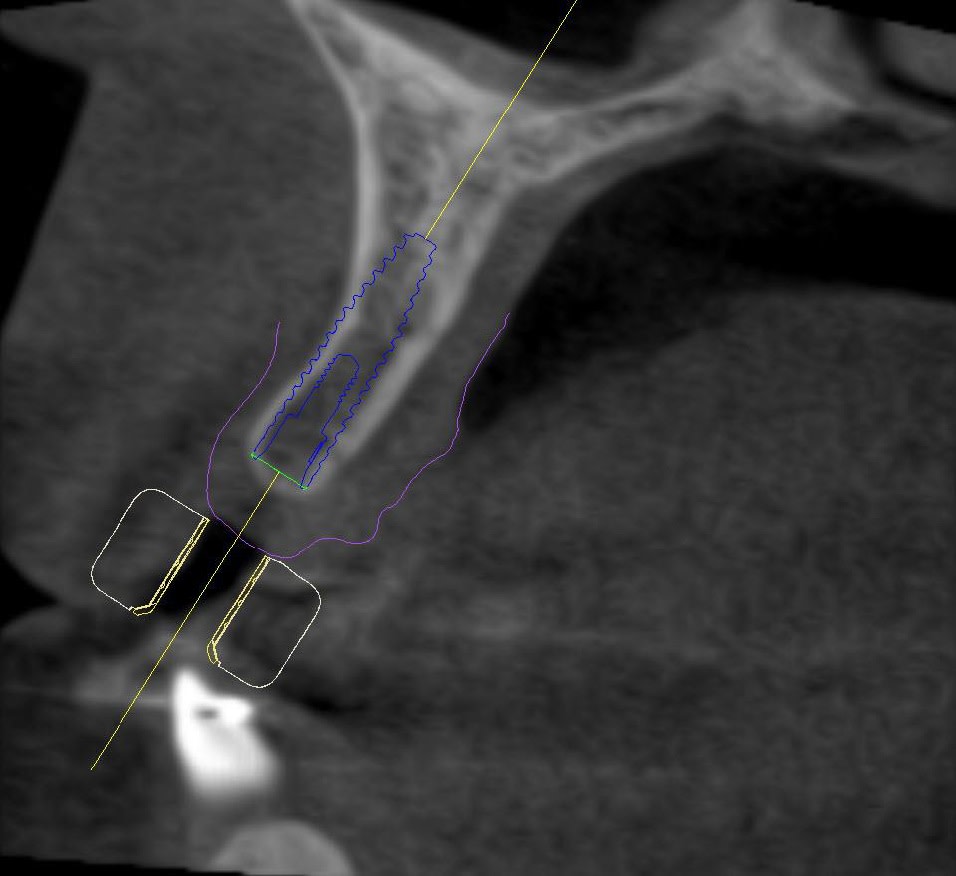

Upon completion of the orthodontic therapy, the gaps between the roots of the adjacent teeth and the crowns of the adjacent teeth were restored. The patient was showing very limited gap widths and unfavorable interradicular space conditions. Initial marginal bone thickness in the gaps was approximately 4.5 mm (Figure 3) with apical thinning (Figure 4 and Figure 5).

After discussing the treatment plan with the patient it was agreed upon that two small-diameter (2.9 mm) implants would be placed in positions 7 and 10, followed by fixed restorations. The position of the implants was carefully assessed using a cone-beam computed tomography (CBCT) technique (Figure 4 through Figure 6), and a 3D surgical drilling template was developed and printed to facilitate the drilling process (Figure 7 and Figure 8). Postoperative temporary prostheses were created to avoid gingival pressure and to secure the position stability of the adjacent teeth (Figure 9).

The patient was prescribed with antibiotic (2x 600-mg Clindamycin for 7 days) and anti-inflammatory (Ibuprofen 400 mg) therapy. Exact positioning of implants was further controlled and confirmed using ultra low-dose CBCT technique (Figure 12 and Figure 13).